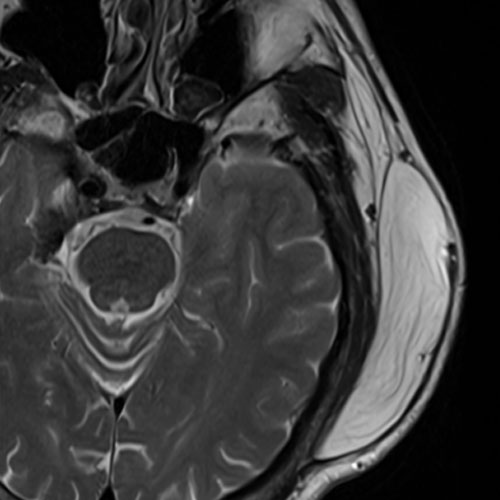

手術前(MRI)

頭の横には大事な血管:浅側頭動脈などがあるので、こちらを注意しなければいけません。